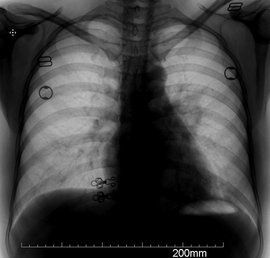

1、 肺根影的中心部位:右肺動脈由左向右橫穿縱隔,在未達肺根區時已分為上、下兩支,這個分支點即為右肺根影中心點。左肺動脈上跨左主支氣管向後與X光方向一致,因而在左肺根影上部形成一個圓形緻密點,這個圓團影的中心,即左肺根影中心點。

2、 肺根影的上下界限:上界----右肺動脈分三個肺階段處,即上部肺血管匯集點。下屆---右下肺動脈背段分支處,右中葉動脈也出發於此。即下部肺血管匯集點。

4、 肺根影的密度:時至今日,對於X光平片的密度核定在X光診斷學中仍屬另一難題。客觀上尚無任何可依的條件、儀器或規律來審定影像的密度差。正位胸片上,左肺根影上部的左肺動脈結節影為肺根影中的最高密度區 。由於與X光線平行行進一個段落。有時會誤診為左上肺根部包塊影。

正位胸片上的次高密度影是右下肺動脈區,由於右下肺較多的肺結構組成。肺根影的最低密度區是右上肺根,雖然左下肺根影常常被心影重疊,但仍可查見其存在。 側位胸片上,肺根影最高密度區是右肺動脈的卵圓形投影。因為它與X光並行了一段距離。

⑶成人左肺根影永遠高於右肺根影。但在小兒則不然。肺根影自新生兒至老年逐漸慢慢地長大;右肺根影較左側為大,這與解剖學完全一致;肺根影各值在女子較男子為小

⑷正位胸片肺根影最高密度區是左肺根上部的左肺動脈投影,由於它的走向與X光一致,因而形成一個緻密圓團影。依同樣原理,右肺動脈在側位胸片的投影也是側位肺根影的最高密度區。